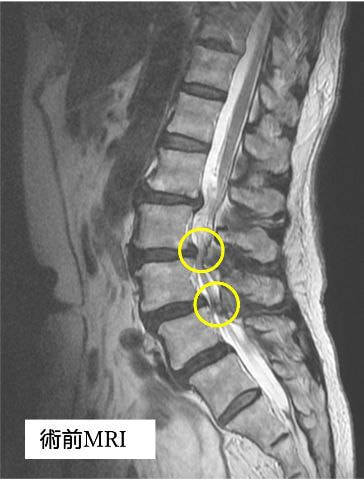

手術の2年ほど前から腰から両殿部痛、下肢後面のしびれが出現し、他院にて腰部脊柱管狭窄症の診断を受けました。徐々に症状は増悪し、手術前は間欠性跛行(※)で長距離の歩行が困難となり、家事を行う際も何度も休憩が必要な状態でした。また、痛みを避けようとするためにかばった姿勢(写真1)となり、筋力低下・可動域制限を認めている部分がありました。その後、手術希望にて当院を受診され、腰椎後方除圧椎体固定術(cortical Bone Trajectory:CBT)が行われました。

術前にあった痛み・しびれは術後2週目にはほぼ消失し、廊下歩行なども積極的に行えるようになりました。術後3週目には屋外歩行を行い、約20分程度の散歩が可能となり、間欠性跛行の改善も得られました。姿勢の改善もみられてました。(写真2)